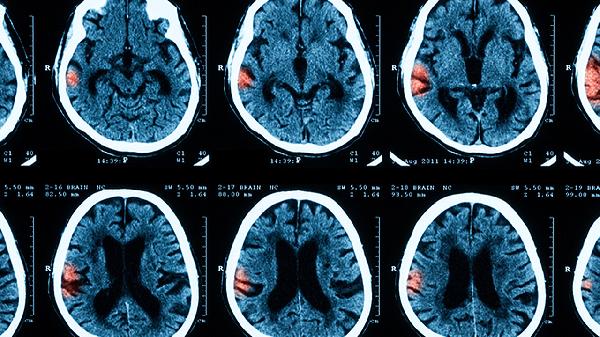

4、影像学评估监测

对于暂未出现神经症状的轻度变形,可通过每月头颅三维CT动态观察钛网形态变化。重点关注钛网边缘是否出现锐利折角、螺钉松动位移等危险征象。磁共振波谱分析有助于早期发现钛网周围脑组织代谢异常。